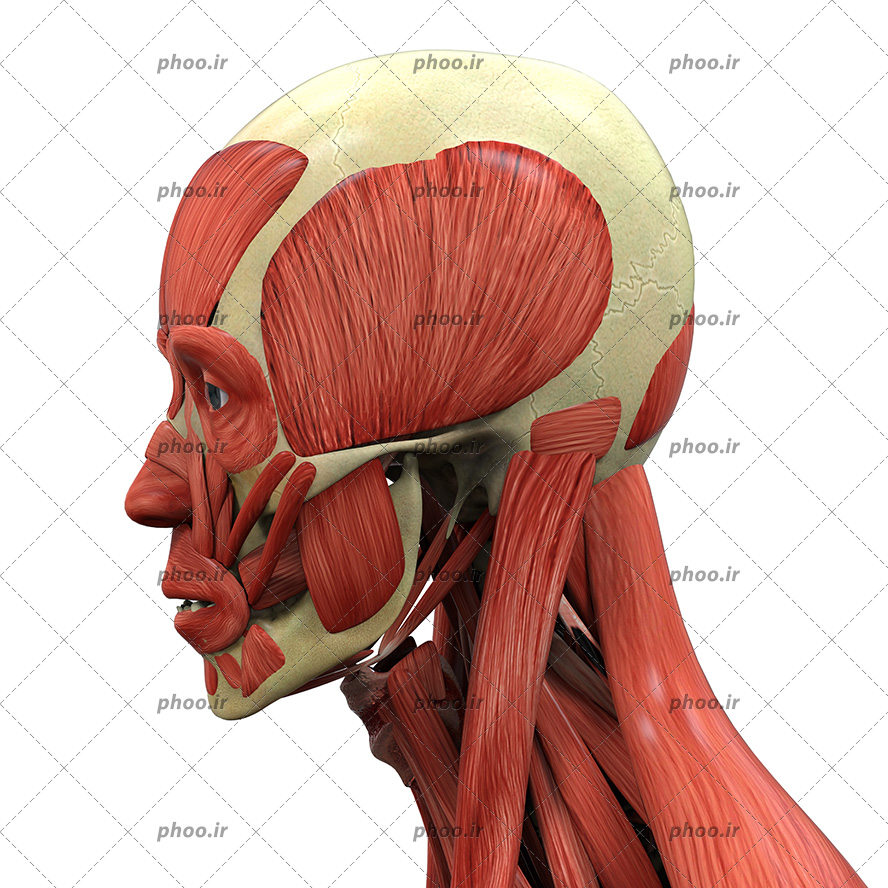

اسکلت جمجمه و گردن انسان ستون فقرات آناتومی اسکلت جمجمه و گردن انسان ستون فقرات آناتومی تصویر با کیفیت را از لینک زیر می توانید دانلود کنید. ۱ مطلب با کلمه ی کلیدی عکس اسکلت بدن انسان با کیفیت ثبت شده است گالری نسیم جدید ترین و با کیفیت ترین عکس های مناسبتی. عکس با کیفیت آناتومی اسکلت بدن انسان و درد و دیسک در قسمت مهره های ستون فقرات کمر ویژه استفاده در امور تبلیغاتی و تجاری طراحی کاتالوگ بروشور و تراکت با موضوع بیمارستان ها و کلینیک ها و درمانگاه ها و مطب ها پزشکان و.